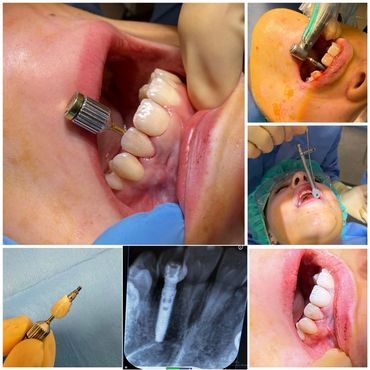

Over the years, I’ve performed 50,000+ extractions and placed more than 3,000 implants, including over 300 full arch immediate loading cases. Every case has taught me something new, and reinforced my belief that surgical dentistry is where I can make the biggest difference.

💡 With ToothOut, I focus on gentle, precise extractions — relieving pain quickly and safely.

💡 With ToothIn, I provide advanced implant treatments — from single implants to full arch same-day smiles.

I enjoy taking on the cases other dentists often avoid — the tricky extractions, complex surgical reconstructions, and challenging full arches. What some see as problems, I see as opportunities to help patients live pain-free and smile with confidence.